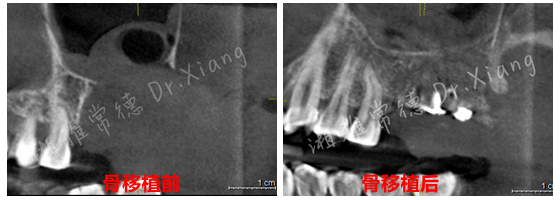

2024年末,该患者因外院不正规的拔牙造成左上颌大面积骨缺损。为寻求颌骨修复,在常德多家医疗机构就诊,均告知难度大建议前往长沙。患者不想奔波,经朋友介绍后来到湘雅常德医院就诊。口腔科主任伍栋接诊了患者并为患者制定了详细的治疗计划。伍栋主任指出:患者因拔牙造成颌骨大面积缺损,目前需要分二步处理。第一,先行颌骨缺损的骨移植;第二,待骨移植成功后,再行缺牙的种植修复。经过周密的术前规划和准备,口腔颌面外科团队在全身麻醉下为患者成功施行了“游离髂骨移植修复术+牙槽植骨成形术”。手术团队巧妙地以患者自身的髂骨作为移植材料,采用数字化3D设计与打印技术,在术中精准截取髂骨并完成上颌骨缺损的定制化重建,成功恢复颌骨及牙槽嵴的生理性高度与宽度,实现解剖结构的精准复原,并应用了微型钛板钛钉内固定系统来确保移植骨的稳定愈合。

经过9个月骨愈合后,患者复查锥形束CT,骨愈合十分满意。9月中旬,向峰医师种植团队成功为患者实施了第二步的手术,取出内固定装置的同时为患者成功微创的植入2枚种植体,完成了患者左上颌区域的软硬组织的自然恢复和改建。